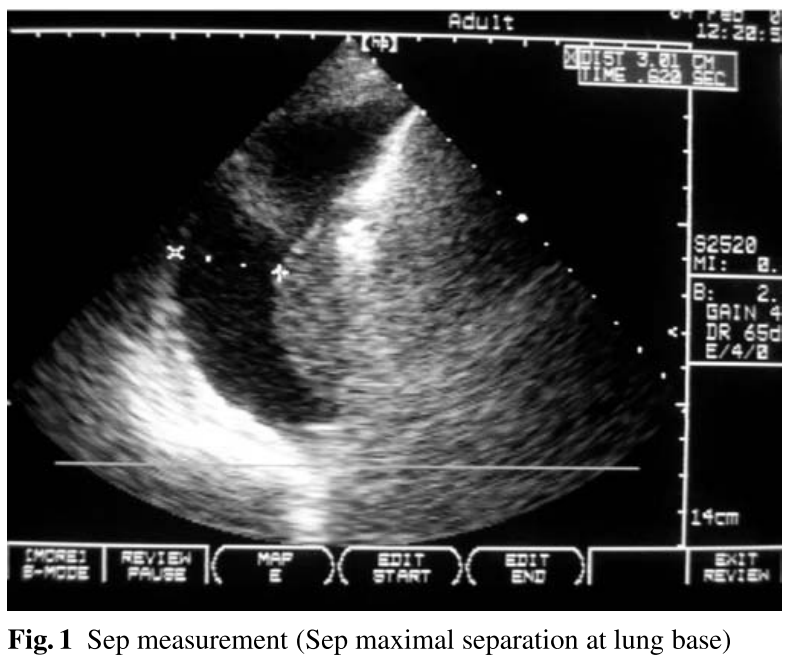

검사를 위해 환자는 supine position에서 상체를 15' 거상한 자세를 취하였습니다. Probe를 posterior axillary line을 따라 이동하면서 검사를 시행하였으며, lung base에서 pleural sepration을 확인하기 위해서 body axis에 수직으로 transverse section을 위치시켰습니다. End-expiration 시 parietal pleura와 visceral pleura의 최대 거리(Sep)를 측정하였다.

Mean Sep은 35 ± 13 mm, mean V은 658 ± 320 ml였으며, Sep과 V 간의 significant positive correlation는 r = 0.72; r2 = 0.52; p < 0.001였습니다. Pleural fluid volume의 양의 추정치는 다음과 같은 공식을 이용했습니다:

V (ml) = 20× Sep (mm)

Lung base는 기계 호흡 중인 환자의 pleural cavity 안에서 종종 consolidation 되고 posterior 쪽에 위치하게 됩니다. 따라서 maximum seperation은 lung과 lateral chest wall 간의 거리를 측정하는 것이, lung과 posterior chest wall 사이에서 측정하는 것보다 정확합니다.